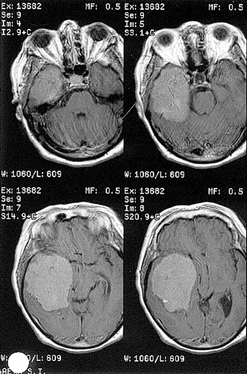

Гиперостотические инфильтративные менингиомы крыльев основной кости представлены, как правило, гиперостозом крыла основной кости различной степени выраженности и мягкотканными компонентами по обе стороны от гиперостоза (рис. 9).

Рисунок 9. Гиперостотическая менингиома крыльев основной кости справа с формированием мягкотканного компонента в глазнице, средней черепной и подвисочной ямках. КТ (вверху) и МРТ (внизу), с контрастным усилением)

Гиперостоз более чем в половине наблюдений распространяется на стенки зрительного канала. Он может вовлекать решетчатую, скуловую, верхнечелюстную кости, чешую височной и лобной костей. Инфильтративная гиперостотическая часть может сочетаться с интрадуральным узлом опухоли. Опухоль часто врастает в верхнюю глазничную щель и передние отделы кавернозного синуса, что ограничивает радикальность операции.